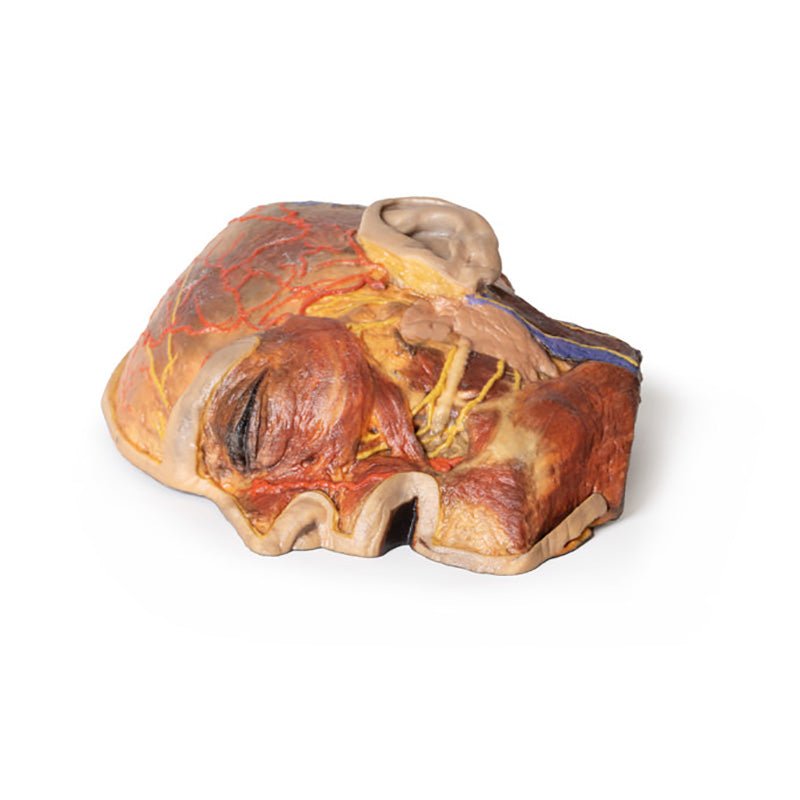

3D Printed Superficial Facial Nerves & Parotid Gland

This 3D model presents the superficial anatomy of the face and head, and compliments the superficial facial anatomy

of our HW 44 model with a more expanded dissection across the scalp and occipital regions.

The superficial

neurovascular and muscular structures in the face largely mirror the structures described in reference to our HW 44

specimen (see description), although the terminal branches of the facial nerve (CNVII) can be largely followed

across a longer course from the parotid gland and the platysma muscle has been retained superficial to the mandible

and extends towards the neck.

In contrast to the HW 44 specimen, this model has a more expansive superficial

dissection inferior to the external ear and across the posterior scalp and occipital region. This allows for an

expanded appreciation of the neurovascular distribution of the supraorbital and supratrochlear nerves and arties

with the superficial temporal artery. Inferior to the ear, the retromandibular vein has been exposed with the

ascending fibres of the great auricular nerve on its superficial surface (and further branches of this nerve on the

surface of the sternocleidomastoid muscle). At the posterior border of the sternocleidomastoid muscle the lesser

occipital nerve is just preserved, near the exiting and ascension of the occipital artery and vein near the

trapezius muscle towards the posterior scalp. Surrounding the external ear are fibres of the auricularis superior

and posterior muscles. Near the margin of the dissection window posteriorly the deep fibres of the occiptalis muscle

can be seen integrated into the epicranius (occipitofrontalis) muscle.